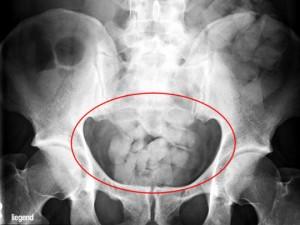

Empiezan a trabajar a las cuatro de la mañana, cuando llegan los primeros vuelos calientes, y terminan a las 10 de la noche. Son 30 policías que cada día, de media, detienen a una mula, bolero, burriel, o correo de la droga…; …un detenido al día de media, y al día, de media, 2 kilos y medio de cocaína interceptada. Dicho eso mismo pero en cifras redondas…: el año pasado detuvieron a 336 personas e incautaron casi una tonelada de cocaína. En lo que llevamos de este año, cerca de 350 kilos de coca y por encima de las 125 detenciones.

Ese es y así es el balance, la hoja de servicios, del Grupo de Estupefacientes de la policía en el aeropuerto Adolfo Suarez-Madrid Barajas…, el principal aeropuerto de entrada de droga… De que no salga del aeropuerto y no se pueda distribuir se encargan ellos, policías de élite y